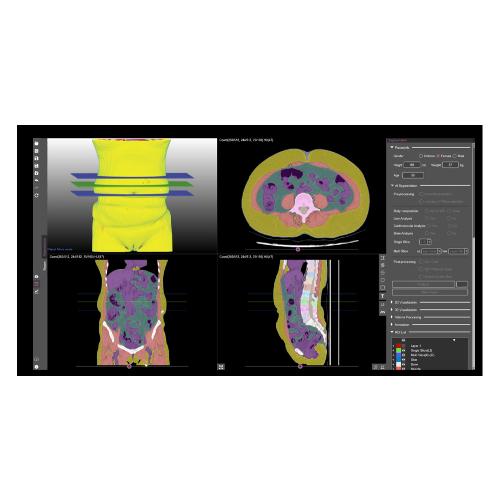

Automatic Analysis of Body Composition Based on CT

Over 7 x-layers in total

(skin, bones, muscles, visceral fat, subcutaneous fat, etc.)

Whole body segmentation

-Skin, bones, muscles, visceral fat, subcutaneous fat, organs, cerebrospinal fluid, etc

-Skin, bones, muscles, visceral fat, subcutaneous fat, organs, cerebrospinal fluid, etc

Automatic segmentation of body composition structures

Automatic analysis of AI-based body composition and provision of quantitative information

High accuracy (97%) & fast analysis rate

(0.16 seconds/slice)